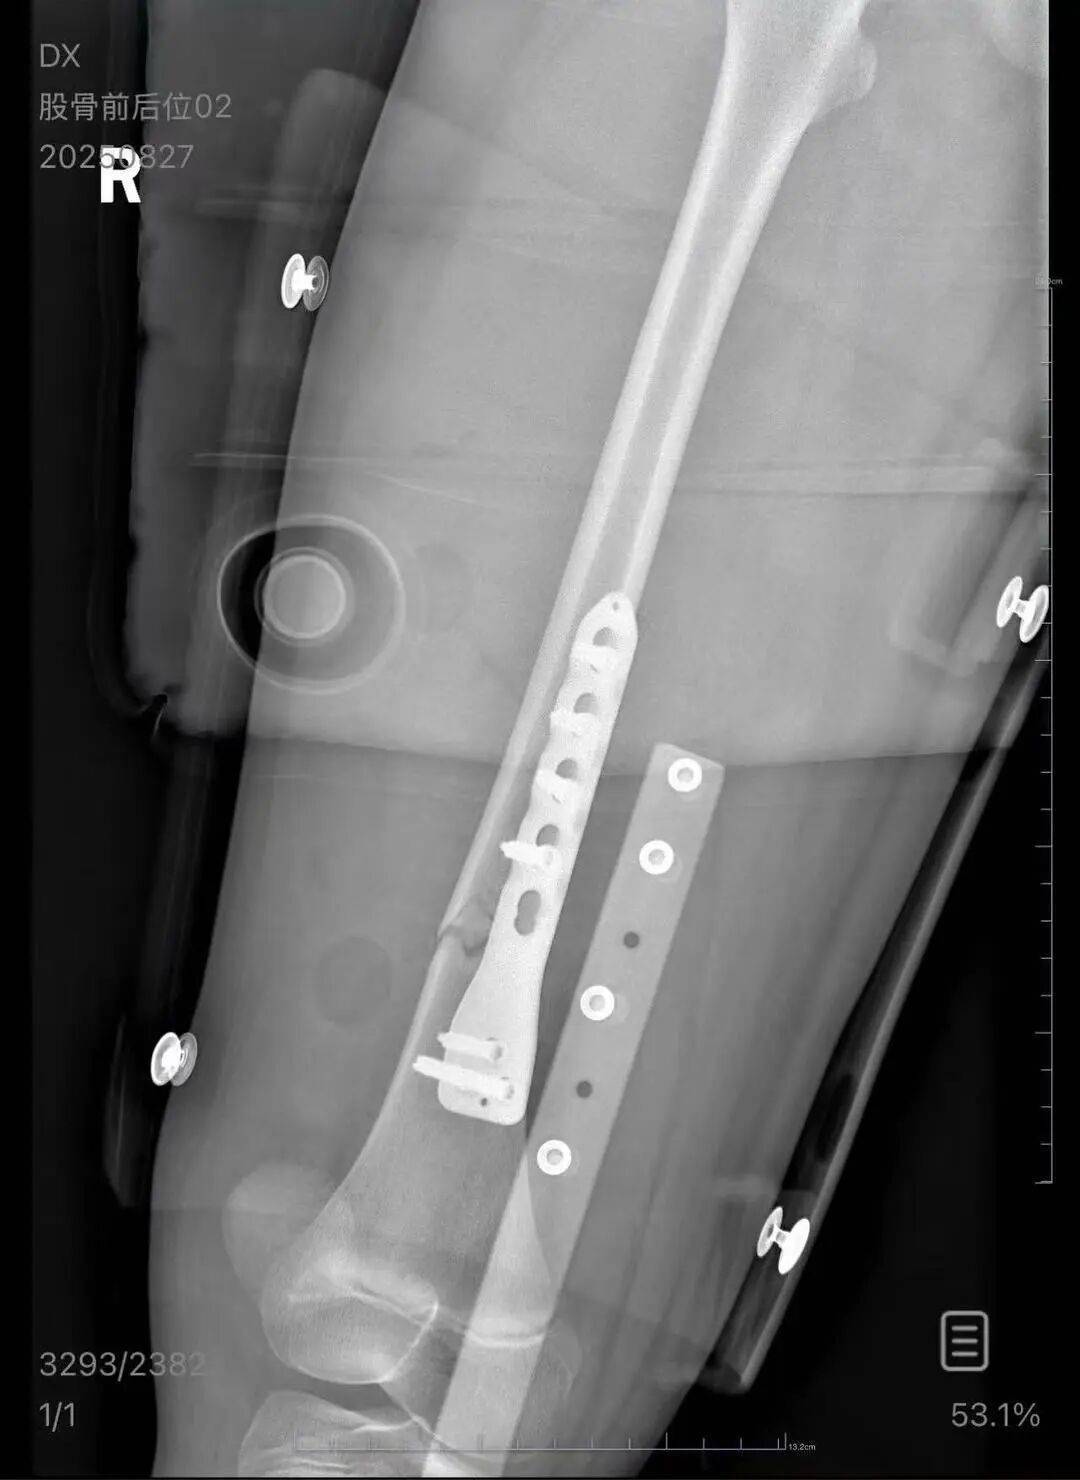

▲朱女士女儿手术后拍的X光片 受访者供图

朱女士向记者出示的医院病历显示,8月24日凌晨,朱女士的女儿到医院就诊XRP行情。医院诊断朱女士的女儿右股骨骨折,需要住院进一步治疗。